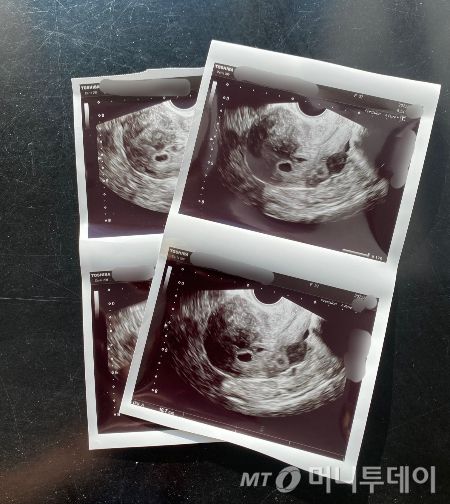

초음파 사진 속 선명했던 '라봄이'의 동그란 아기집. 그걸 보고, 이제 엄마·아빠가 된다며 기뻐했을 이들. 집을 잘 지어봤으니, 다음엔 꼭 그 튼튼한 집에 예쁜 아가가 찾아올 거라고. 그리고 "엄마·아빠, 제가 조금 늦었어요"라며 건강하게 바깥에 나올 거라고./사진=독자님 제공. |

안녕, 라봄아.

초겨울에 네가 선물처럼 찾아왔어.

봄을 기다리는 마음으로

'라봄이'라고 너를 부르기로 했지.

섣불리 너를 반기는 건 아닐까 내심 걱정도 됐지만,

남편과 나의 8년 결혼생활에 찾아온 널

초음파로 처음 만난 순간

사실 이루어 말할 수 없을 만큼

신기하고 행복했단다.

그 뒤로 매일같이 그리는 우리의 미래엔

네가 빠진 적이 단 한번도 없었어.

아침에 눈을 뜨면 희망감에 차올랐고,

소심하고 겁 많은 나에게

왠지 모를 강단도 생기는 기분이었지.

그런 네가 엄마 뱃속에 집만 지어놓고 떠났다는구나.

진료실을 나와 배부른 엄마들 사이에서

아빠와 참 오래도 울었단다.